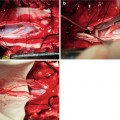

The parasympathetic autonomic efferents from sacral spinal cord to bladder detrusor are generally considered lying in S2-4 ventral roots. In surgery, it is very important to determine the innervative frequency and efficacy of every individual nerve root when operation is performed on the sacral roots. We performed those operations in ten cases of Chinese with complete supraconal spinal cord injuries. There were seven men and three women, with an average of 32 years old. Our results show that pressure contributions are provided by S3 roots in all ten patients, bilaterally; and by S4 roots on the right side of ten patients and left side of eight patients. However, only three have minimal pressure uprising by S2 stimulation, one on the right side and two on both sides. The mean innervative efficacy by differential sacral roots to bladder detrusor is shown in Fig. 11.1. S3 root is the most frequent and the most efficacious contributor, S4 is the second frequent and a lesser but still significant efficacious one, and S2 is the last frequent and the minimal contributor(Fig. 11.2) [20]. The right roots seem to be stronger than the left ones. The efficacy distribution of sacral root innervation to bladder detrusor obtained by us is similar to that by Brindley, but the innervative frequency is different. Rising in bladder pressure is obtainable always by stimulating S3, usually by S4, and often by S2 in Europeans; however, it is always by S3, usually by S4, and seldom by S2 in Asians [20].

Fig. 11.2

Differential sacral roots innervation to bladder detrusor in Asian people